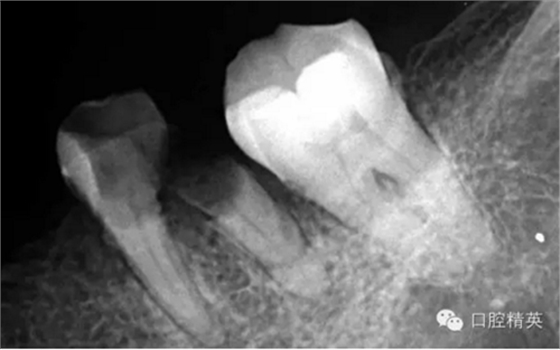

這個(gè)病例是我準(zhǔn)備分根的病例,保留近中根,曾在外院做過干尸長(zhǎng)達(dá)數(shù)十年。8號(hào)挫疏通時(shí)近舌根堵,近頰未找到。在這個(gè)病例中首先要知道是為什么根管難以疏通,首先是長(zhǎng)時(shí)間的干尸,和患者年紀(jì)較大根管逐漸變窄,根管道路可能會(huì)出現(xiàn)堵塞,在這張病例中我能知道的是稍有不慎就會(huì)形成臺(tái)階,從而導(dǎo)致根管堵塞加重,更加難以疏通。

近舌8號(hào)k挫疏通,根尖部彎曲,我花費(fèi)時(shí)間2小時(shí)疏通。我個(gè)人覺得根管能否被疏通,第一個(gè)重要因素是時(shí)間,因?yàn)樽鳛檠荔w牙髓的醫(yī)生,首先就是需要的就是耐心。我個(gè)人覺得耐心是非常重要,因?yàn)楹芏喔鼙皇柰〞r(shí),都是我們快要放棄的時(shí)候。所以我每次都會(huì)安慰自己快好了,快好了,就差一點(diǎn)點(diǎn),在堅(jiān)持一會(huì)兒就好了。可以說(shuō)沒有耐心,想做好牙體牙髓,我個(gè)人覺得很難很難。第二個(gè)就是手法,不知道大家啟用挫是什么挫,一般我個(gè)人認(rèn)為,最好從8號(hào)開始疏通,這樣不容易在狹窄的根管內(nèi)形成臺(tái)階(如果有條件的可以從6號(hào)開始)。